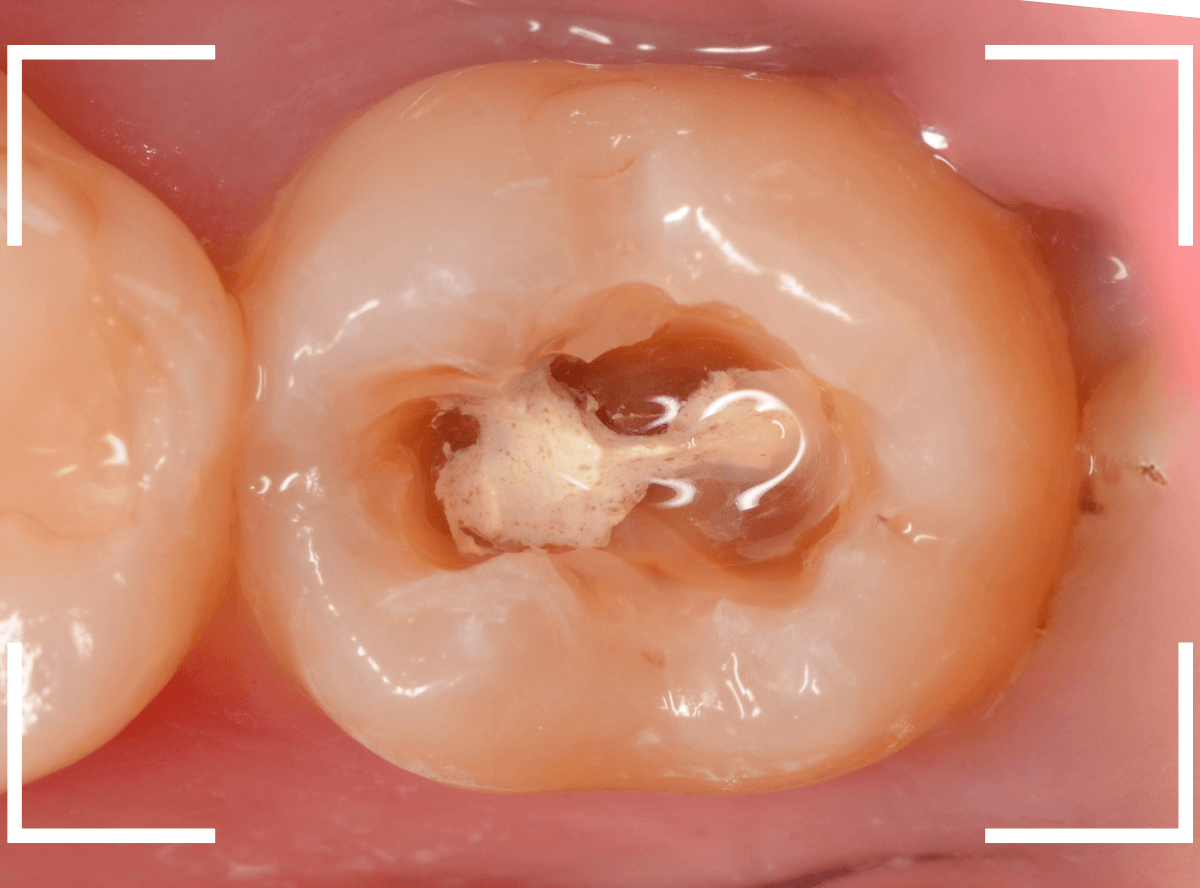

「つめものが欠けたまま長期間放置して、歯がしみる」という訴えで来院された患者さんさんです。

拝見すると、劣化したレジンが欠けて、中で虫歯になっているのがわかります。

・欠けたまま長期間放置した

・しみるという自覚症状がある

事から、中で深い虫歯になっている事が想像されます。

レントゲン写真で確認します。

レジンを外しながら、虫歯を確認します。

慎重にレジンを除去しましたが、途中で露髄(神経が露出する事)しました。

歯の神経の中には、血管も含まれているので、神経が露出すると、このように出血します。

「しみる、痛い」などの明確な強い症状がある場合、このような状況の事が多いです。

今回は出血量が多く、神経を除去する治療(抜髄)の可能性が高いとも感じましたが、できる限り神経を保存する方法を取ることにしました。

神経を保護するお薬をつめて蓋をしてしばらく経過観察します。

神経を除去すると、治療期間が長引くうえに、歯の寿命がとても短くなってしまいます。